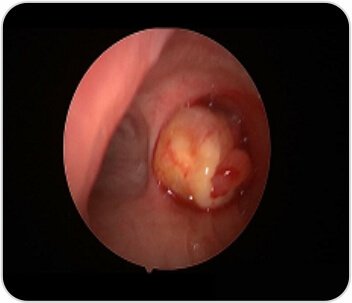

Bronchoscopy revealed near complete occlusion of the right main bronchus with a mass. Tumor was arising from the right lower lobe- basal segment. She was intubated with rigid bronchoscope and the tumor debulking was done with electrosurgical snare and 1.1 Cryo Probe. Post procedure complete patency of right bronchus was achieved. Patient’s symptoms improved after the procedure

Bronchoscopic image showingintra bronchial tumor (Before)